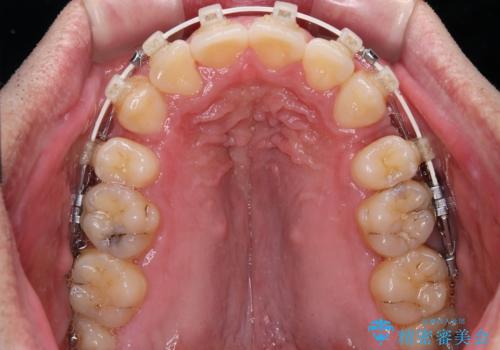

- 矯正装置

- 審美装置

上顎歯列幅を側方に拡大するとともに、歯列全体を後方に移動させるためのアンカースクリューと補助装置を使用し、上顎左右第一小臼歯2本、下顎左右第二小臼歯2本、計4本を抜歯し、ワイヤー装置にて矯正治療を行うこととしました。